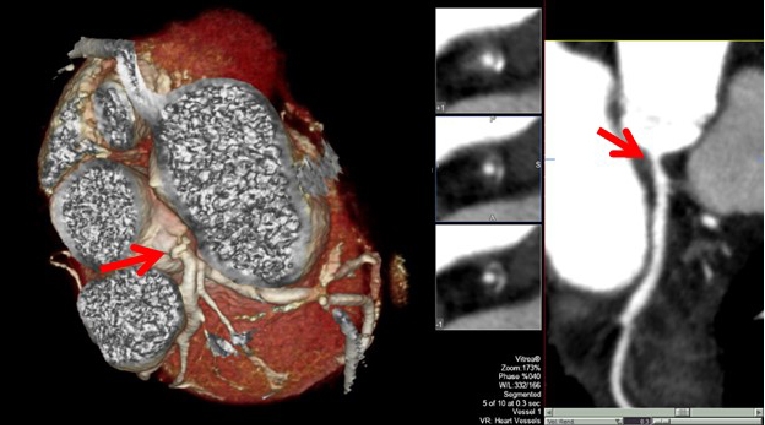

Radiotherapy is an independent risk factor for microvascular endothelial inflammation implicated in the pathogenesis of accelerated atherosclerosis and heart failure, usually associated with preserved ejection fraction [15]. The risk of radiation-induced CAD is directly related to radiation doses, increases over time and is magnified by the presence of CV risk factors. Usually the distribution of CAD reflects the radiation field: typically, lesions are clustered in a proximal distribution, increasing the risk of larger myocardial infarctions even in young patients without traditional cardiac risk factors (Figure 1) [15]. A large Scandinavian case control study in over 2,000 patients with breast cancer showed a linear relationship between mean heart dose and the risk of an ischaemic event. The risk of a major coronary event increased by 7.4% per gray mean dose to the heart and no dose threshold could be observed [17]. The increase started within the first five years after radiotherapy and continued to increase over decades. For example, for a 70-year-old woman without CV risk factors receiving a mean heart dose of 10 gray, her cardiovascular risk increases to a similar extent as having an established CV risk factor without having received radiotherapy. In a recent study; it has been shown that especially the dose received by the LV was a better predictor of acute coronary events compared to the mean heart dose [18]. The increased risk for CAD highlights the importance of assessing CV risk factors in patients treated with radiotherapy; however, it is unclear whether a screening programme (e.g., coronary CT angiography in patients exposed to radiotherapy) may be beneficial. Since treatment with radiotherapy is an important risk factor for CAD, it seems prudent that CV risk factors, including hypercholesterolaemia and hypertension, should be treated aggressively along with lifestyle interventions [2,3,16].

Figure 1. Clinical case. A 42-year-old female presented to the cardio-oncology clinic complaining of mild chest pain and transient dizziness during sports practice. The patient had a history of Hodgkin’s disease treated with anthracycline-based chemotherapy and mediastinal radiotherapy at 16 years old. She had no other CV risk factors. Baseline electrocardiogram revealed sinus rhythm with no associated repolarisation abnormalities. Echocardiographic examination showed an LVEF of 57%. Non-invasive coronary imaging using computed tomography angiography revealed a non-calcified significant lesion at the left main coronary artery. Subsequent cardiac catheterisation revealed severe disease in the left main coronary artery. A drug-eluting stent was placed without associated complications. The patient was discharged under aspirin, prasugrel and atorvastatin. She remains asymptomatic at follow-up.